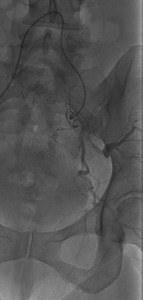

On POD #50 from the hysterectomy, the patient presented to the office with persistent vaginal cuff bleeding, less brisk than prior presentation. There were no sources of bleeding identified on exam. The patient then underwent a CT scan without any evidence of intraabdominal bleeding. Given persistent bleeding without a clearly identifiable source, the decision was made to proceed with bilateral embolization of the anterior divisions of the internal Iliac arteries. The embolization led to resolution of the vaginal cuff bleeding.